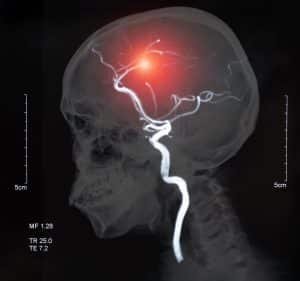

According to a recent article published in The Washington Post, a study reveals that there is a risk of a very common type of stroke for people who fall and bump their heads and develop a traumatic brain injury. This common type of stroke is called an ischemic stroke, which accounts for more than 80 percent of all stroke cases in the United States. Ischemic strokes occur when the brain cannot get the blood supply it needs. This typically happens when a vessel becomes blocked, preventing the necessary nutrients and oxygen from making its way to the brain. Unfortunately, when the vessels become blocked, the brain cells can start to die quickly.

Another study released in the National Library of Medicine a few years ago also analyzed individuals who have and have not experienced traumatic brain injuries. After the study ended, the researchers determined that it does not matter how minor or severe a person’s traumatic brain injury is or even the type of traumatic brain injury that they experience (concussion, diffuse axonal injury, contusion, etc.). Anyone who suffers a traumatic brain injury is at risk of an ischemic stroke. The study also pointed out that when an individual experiences a traumatic brain injury, they are 86 percent more likely to have a stroke within the first few months than individuals who have never suffered a traumatic brain injury.

If your loved one is having a stroke or you suspect that they have already had a stroke, prompt diagnosis and treatment is essential. This means that a doctor will need to quickly assess the person’s body, determine their medical history, and order imaging scans of the brain. Imaging scans will allow the doctor to see if there is anything out of the ordinary happening with the brain. For example, they may be able to locate if your loved one has a traumatic brain injury, any reduction of blood flow to the brain, or any bleeding on or within the brain.